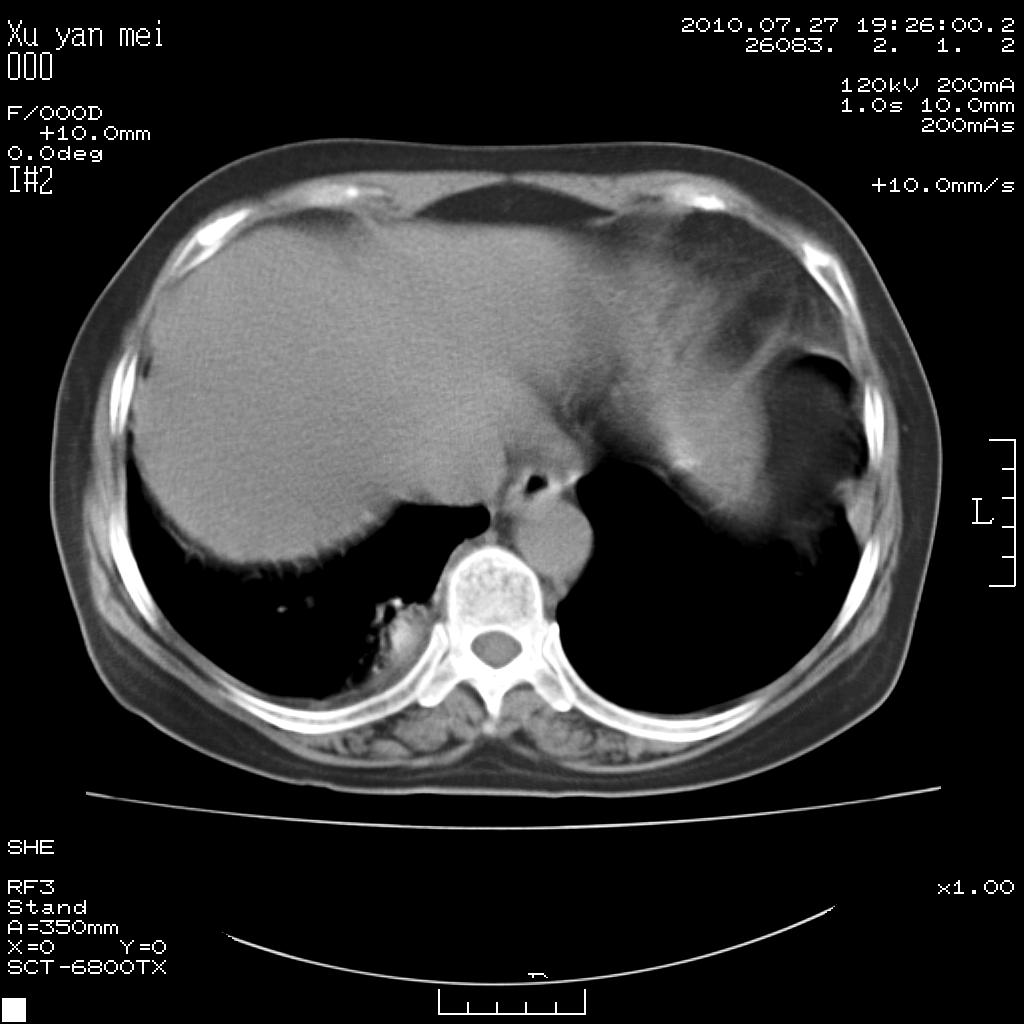

女,60岁,胸痛就诊,右肺结核?炎症?其它?(胸片右侧中上肺野确实看不到什么啊)

1)考虑两肺感染性病变;建议抗炎治疗后复查。2)双侧少量胸腔积液。

1)考虑两肺感染性病变;建议抗炎治疗后复查。2)右侧少量胸腔积液。

右侧少量胸腔积液,段性肺炎。

双肺炎症可能性大,建议抗炎后复查。右侧胸腔少量积液。双侧胸膜轻度增厚。

考虑两肺感染性病变;不除外肺栓;建议抗炎治疗后复查。